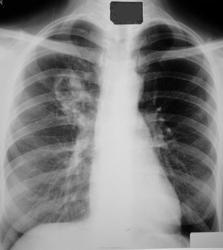

Молодой мужчина (1979 гр) поступил в инфекционное отделение с рабочим диагнозом пневмония.

Клинически - последние 2 недели беспокоит малопродуктивный кашель с трудноотделяемой мокротой, слабость, температура до 38.

Формально в д/д ряду наиболее вероятны круглый туб инфильтрат (туберкулёма) и неопластический процесс.

Кольцевидная тень верхней доли правого легкого с неравномерной стенкой, наибольшей по толщине с "1 по 3 ч", полостью распада с неровным достаточно ясным контуром. Секвестров не отмечено. Внешний контур также ясный (термин, невилирующий разницу между "размытый" и "четкий"). Видны перифокальные очаги мелких и средних размеров ниже и медиальнее "кольца". Перибронхиальная инфильтрация прилежащих бронхов. В дифф.ряд поставил бы всё выше указанное с акцентом на инф.туб. с распадом.